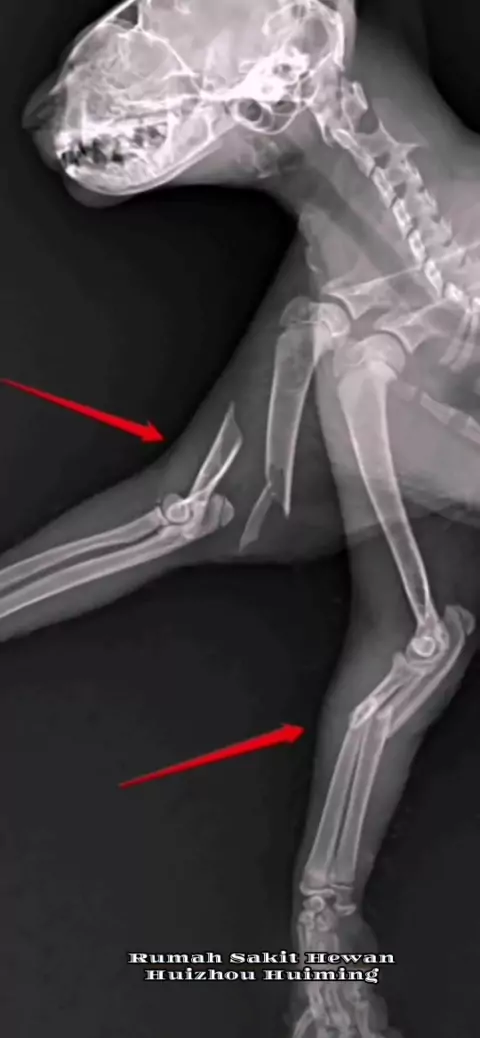

Kucing oranye kecil itu secara tidak sengaja jatuh dari gedung dan beberapa patah tulang dan sekarat. Dia adalah anak kucing liar yang diadopsi oleh pemiliknya, dan pemiliknya tidak menyerah pada biaya pengobatan yang tinggi. (Senang memiliki pemilik yang bertanggung jawab) # Pet Hospital